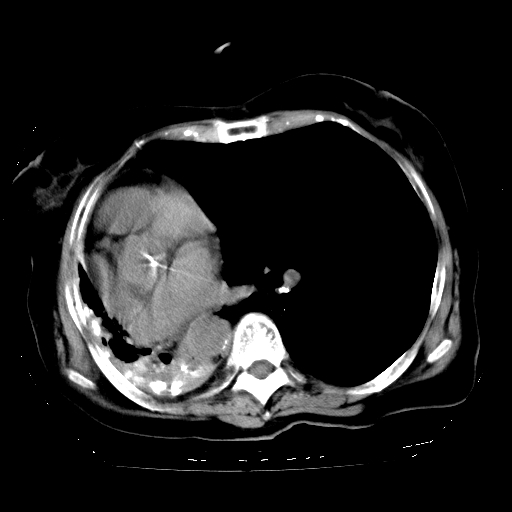

标题: CT23991:女,72岁,咳嗽、憋气一周。 [打印本页]

女,72岁,咳嗽、憋气一周,十年前曾患肺结核及胸膜结核。

右侧毁损肺,右侧纵隔疝

右侧毁损肺,右侧纵隔疝,左肺代偿!

1.右侧损毁肺伴胸膜钙化,2.左肺小结节灶,良性可能大,注意复查。3.肝脏左叶囊肿。4.先天性一侧肺不发育待出外(右侧胸廓无明显塌陷)。对比原片应该非常有帮助。